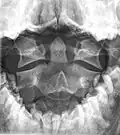

In anatomy, the axis (from Latin axis, "axle") is the second cervical vertebra (C2) of the spine, immediately inferior to the atlas, upon which the head rests. The spinal cord passes through the axis.

The defining feature of the axis is its strong bony protrusion known as the dens, which rises from the superior aspect of the bone.

The dens, also called the odontoid process, or the peg, is the most pronounced projecting feature of the axis. The dens exhibits a slight constriction where it joins the main body of the vertebra. The condition where the dens is separated from the body of the axis is called os odontoideum and may cause nerve and circulation compression syndrome.[1] On its anterior surface is an oval or nearly circular facet for articulation with that on the anterior arch of the atlas. On the back of the neck, and frequently extending on to its lateral surfaces, is a shallow groove for the transverse atlantal ligament which retains the process in position. The apex is pointed and gives attachment to the apical odontoid ligament. Below the apex, the process is somewhat enlarged and presents on either side a rough impression for the attachment of the alar ligament; these ligaments connect the process to the occipital bone.

The internal structure of the odontoid process is more compact than that of the body. The odontoid peg is the ascension of the atlas fused to the ascension of the axis. The peg has an articular facet at its front and forms part of a joint with the anterior arch of the atlas. It is a non-weight bearing joint. The alar ligaments, together with the apical ligaments, are attached from the sloping upper edge of the odontoid peg to the margins of the foramen magnum. The inner ligaments limit rotation of the head and are very strong. The weak apical ligament lies in front of the upper longitudinal bone of the cruciform ligament and joins the apex of the deltoid peg to the anterior margin of the foramen magnum. It is the fibrous remnant of the notochord.